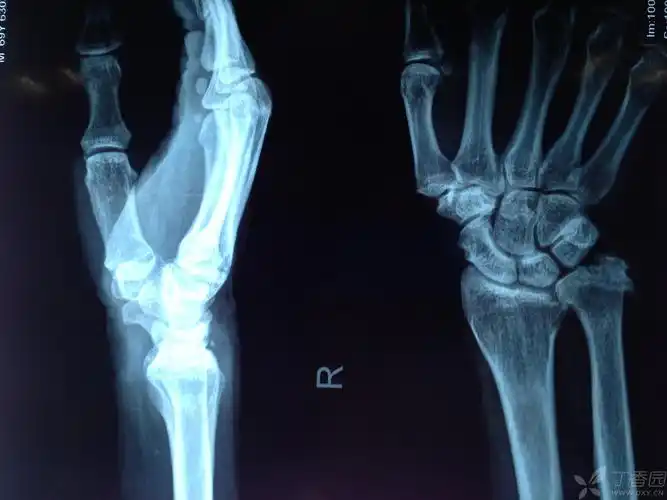

尺骨骨折不愈合

右尺骨骨折

右尺桡骨茎突骨折月骨周围脱位